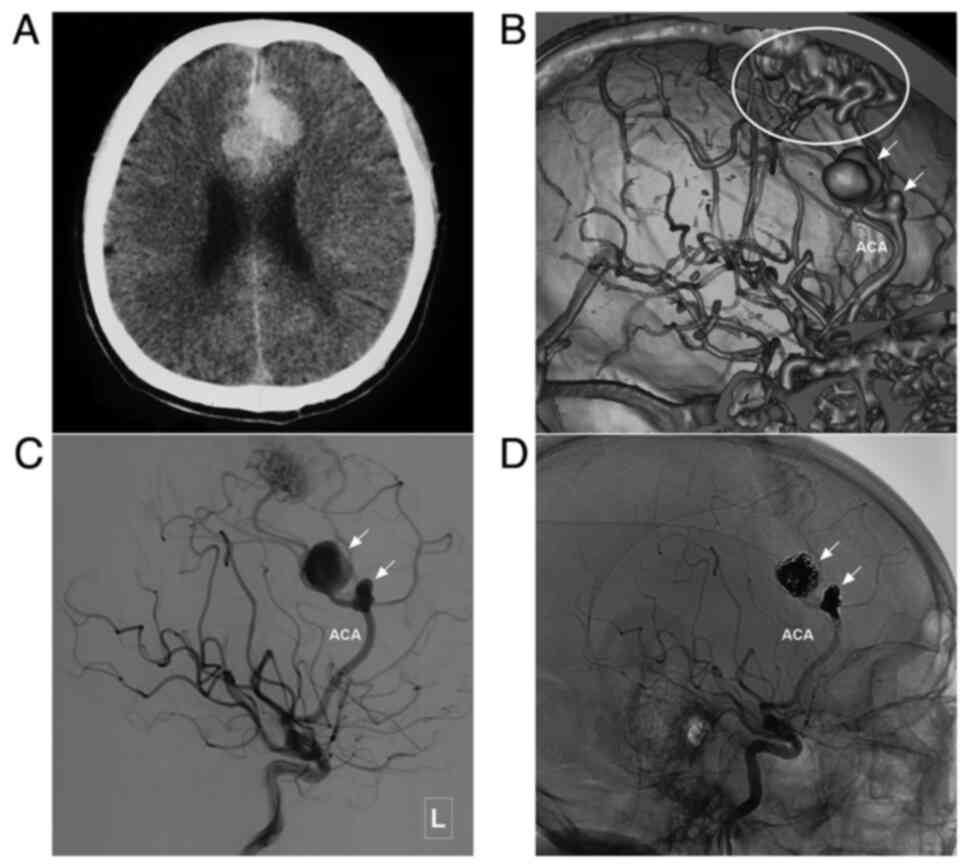

Figure 3

Typical case of a type I ACA-BAVM with flow-related aneurysm. (A) Head CT scan illustrating a subarachnoid hemorrhage in the interhemispheric fissure with hydrocephalus. (B) Head CTA scan illustrating an aneurysm (arrow) located in a branch of the ACA. (C) Angiogram of the right internal carotid artery in lateral view indicates a flow-related aneurysm (arrow) in the feeding artery of an ACA-BAVM. The BAVM is supplied by multiple branches (asterisk) of the ACA. (D) X-ray of the cranium indicating Onyx casting (encircled area) following embolization. (E) Angiogram of the right internal carotid artery after embolization illustrating that the aneurysm in the feeding artery is embolized. There is some remnant of the BAVM (encircle area) and some feeding arteries (asterisk). (F) Post-treatment CT scan illustrating that the patient undergoes external ventricular drainage. ACA, anterior cerebral artery; BAVM, brain arteriovenous malformation; CT, computed tomography; CTA, computed tomography angiography; R, right.